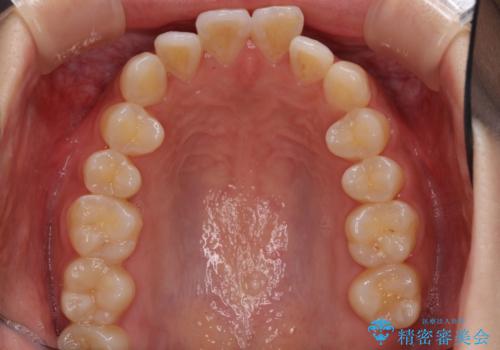

前歯のデコボコと突出感 インビザラインで改善

- 上下前歯のデコボコを気にして来院された患者様です。

インビザラインによる上下歯列の側方拡大と後方移動、IPR(歯と歯の間を削る)にるスペースの獲得により歯列を整えることとしました。